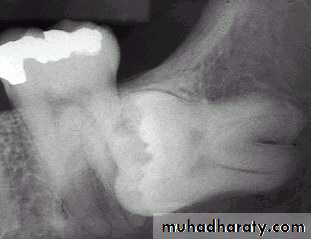

2 – prevention of Dental caries

E.g Dental caries can occur at the lower 8 or

adjacent lower 7 most commonly at the

cervical line due to the inability of the patient

to clean the area thoroughly .